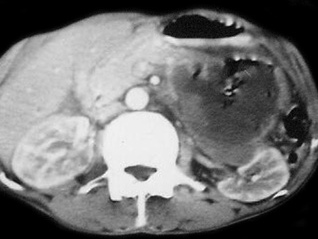

hydatis-

318 × 239